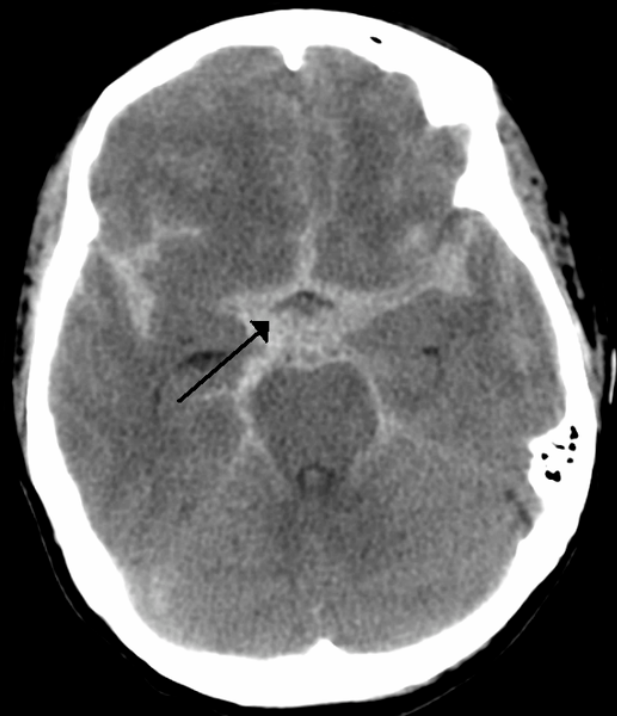

what does this CT head show?

A

subarachnoid haemorrhage